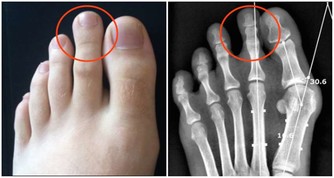

***1.水腫***

一般腎功能衰弱的人體內累積過多水份而無法排泄出去,會形成水毒。當你早上起床時發現眼瞼或面部水腫,午後就會消退,勞累後加重,休息後又減輕了。

嚴重時,水腫可出現在身體低垂部位,如雙腳踝內側、雙下肢、腰骶部等,這些症狀長期反覆出現,尤其是40歲以上的人更應該要注意,你的腎臟是不是出現了問題。